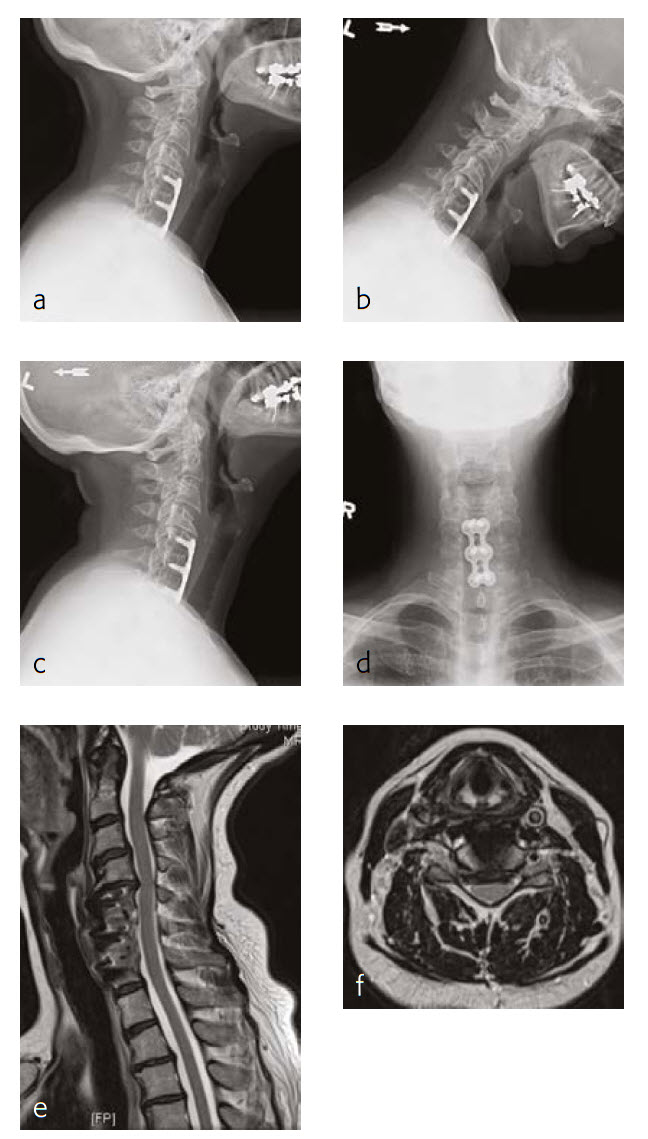

Case 2: Neck pain with cervicogenic headaches

The patient works at a grocery store as a produce stocker and has a history of C5 through C7 ACDF done in 2005 (Fig 3). Her symptoms were relieved at that time, but she had quite severe neck pain and bilateral radicular symptoms. She had chronic C6 radiculopathy since recovery from that procedure, however, was able to return to work. Unfortunately, over the last 34 months, she has had a recurrence of symptoms, with constant neck pain and occasional cervicogenic headaches.

She will occasionally get bilateral pain, a pins and needles-type sensation through a number of distributions, including C5 through her shoulders, less occasionally through a C7 or C6 distribution. Movement of her neck was becoming increasingly painful, particularly with flexion and lateral flexion to the right and left.

She has tried a number of conservative modalities including narcotic pain medications, rest, heat, ice, physical therapy-type exercises, activity avoidance, and oral steroids. She states that she has had a steroid injection. These were not helpful for her. Eventually, she got an MRI and was found to have adjacent level disease.

On manual muscle testing, the patient had 5/5 strength bilaterally with shoulder abduction, elbow extension and flexion, wrist extension and flexion, finger abduction and grip strength.

The patient has appropriate range of motion through her cervical spine with flexion and extension, and lateral flexion and rotation. She gets grimacing pain with extreme ends of flexion as well as bilateral rotation and lateral flexion. She has no tenderness to palpation of the spinous process or paraspinous musculature of her cervical spine. She has decreased sensation in bilateral C5 distributions.

Follow-up (6 months)

The patient is now about 6 months status post a C4-C5 discectomy and interbody fusion with removal of preexisting C5 screws (Fig 4). She was recovering well and has not been taking any narcotic pain medication. She takes acetaminophen.